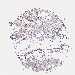

CANCER BREAST CANCER Show tissue menu

BRCA TCGA BRCA VALIDATION PROTEIN EXPRESSION

ANTIBODIES

AND

VALIDATION